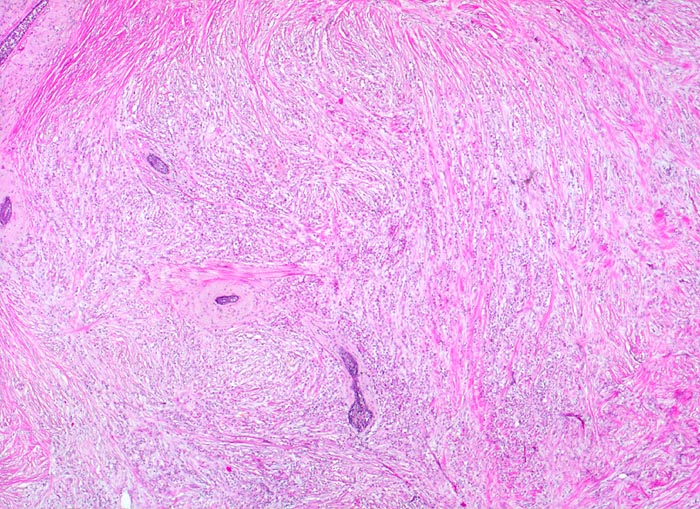

PathoPic – image database / PathoPic ID 4221 - invasiv lobuläres Karzinom

invasiv lobuläres Karzinom

maligner Tumor

Mamma

Die Tumorzellen bilden keine Drüsen, sondern sind hintereinander zu Strängen angeordnet. Diese liegen eingebettet in reichlich desmoplastisches Stroma. Stehengebliebene Gänge werden von den Tumorzellen "umflossen".

25